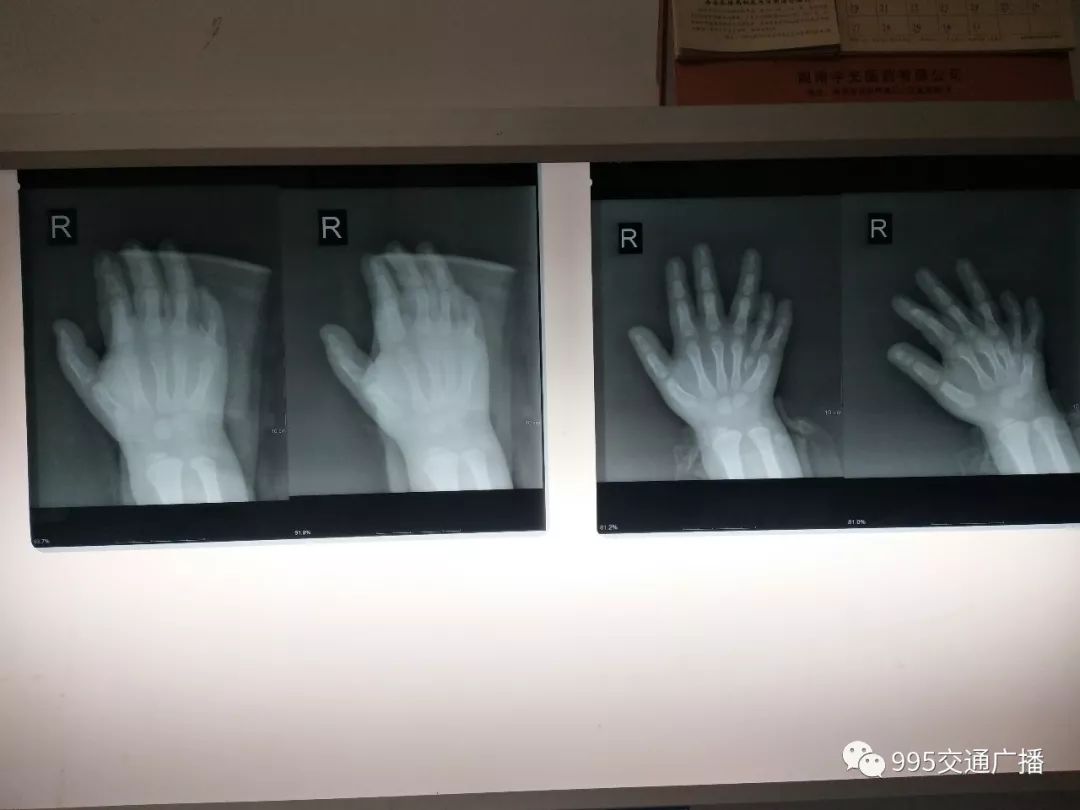

萌萌是一名八岁的小男孩,他的手脚都是六指常遭到同学取笑。为让萌萌身心健康成长,前两天,家人带他到了浏阳年轮骨科医院做矫正手术。经检查发现,萌萌的小指和“第六指”发育都不是很完整,指骨有缺陷。

为确保手术后手指功能不受影响,医生决定对萌萌实施“嫁接”手术,也就是将两根手指发育较好的部分进行扦插嫁接起来。经过两个小时的手术,萌萌的双手手指矫正同时完成,目前术后恢复良好。待双手恢复正常后,再对双脚的指头进行矫正。